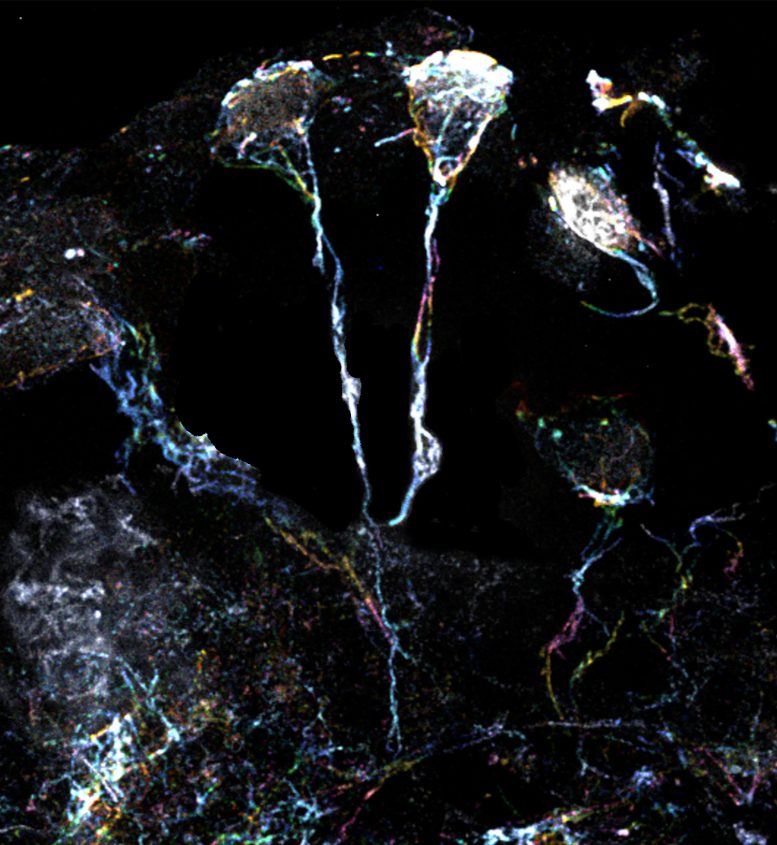

科學(xué)家團(tuán)隊(duì)使用放大倍數(shù)為10倍的超分辨率顯微鏡檢查了果蠅休眠神經(jīng)干細(xì)胞的標(biāo)志性微小纖維結(jié)構(gòu)。這些細(xì)微結(jié)構(gòu)的直徑約為1.5μm(比人類頭發(fā)的直徑小20倍),是從細(xì)胞體延伸出來(lái)的突起,富含肌動(dòng)蛋白或蛋白質(zhì)細(xì)絲。一種特定類型的Formin蛋白可以激活這些細(xì)絲并使其組裝。